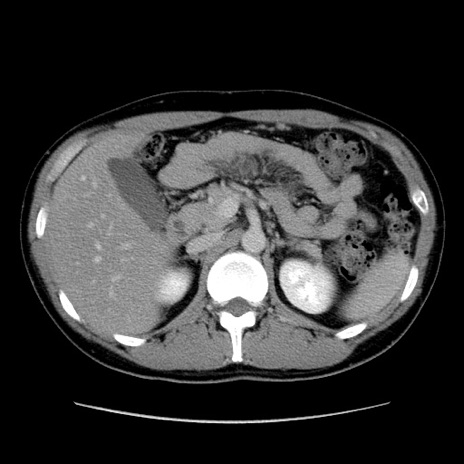

症例36(横断像)

【症例】20歳代 男性

【主訴】心窩部痛

【現病歴】今朝より上腹部痛あり。一旦軽快していたが再度出現したため救急要請。昨日夕に白身の魚を含む刺身を食べた。

【身体所見】BP 136/89mmHg、HR 74/min、BT 37.0℃、腹部:膨満、軟、心窩部に圧痛あり。反跳痛なし、筋性防御なし、腸雑音やや亢進あり。

【データ】WBC 17700、CRP 0.48